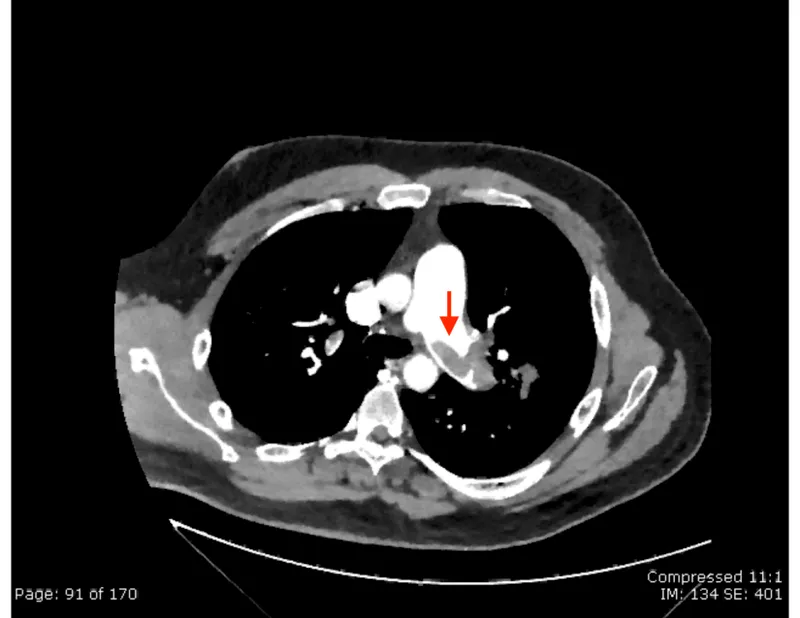

- Diagnosis:

Criteria Pts DVT signs 3 PE #1 Dx 3 HR >100 1.5 Immob/Surg <4wk 1.5 Prev DVT/PE 1.5 Hemoptysis 1 Malignancy 1 - D-dimer (rules out in low prob.), CTPA (gold standard), V/Q scan (if CTPA C/I).

- ECG: S1Q3T3 (📌), RBBB, sinus tachy. CXR: Often normal; Westermark sign, Hampton's hump.

- Diagnosis: V/Q scan (key screening: mismatched perfusion defects); confirm: RHC, CTPA, pulmonary angiography.